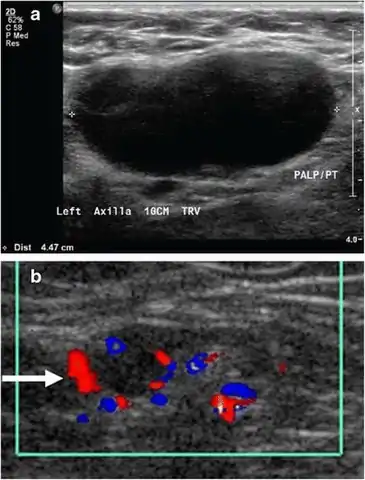

Superficial soft tissues

Doppler ultrasonography can help distinguishing benign from malignant soft tissue lumps.[15] Power Doppler is useful in assessing tendon and joints inflammation such as paratenonitis.[16]

15. 1 2 Dialani V, James DF, Slanetz PJ (April 2015). "A practical approach to imaging the axilla". Insights into Imaging. 6 (2): 217–29. doi:10.1007/s13244-014-0367-8. PMC 4376818. PMID 25534139. Creative Commons attribution license